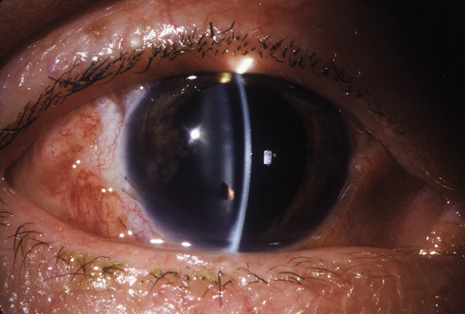

Although keratocentesis had been advocated historically as a treatment for active uveitis, it lost the attention of ophthalmologists until 1919, when Bruckner3 first examined the aqueous humor for diagnostic purposes. Laboratory techniques were revolutionized in the 20th century in areas such as: (a) evaluating very small aliquots of fluid (0.2 to 0.3 mL of aqueous or vitreous), and (b) identifying specific microbial organisms and the predominance of other cell types, antibodies, and proteins in these fluids (Figs. 1, 2, 3, 4, 5, and 6). These advancements have led to the development of diagnostic paracentesis for sight-threatening ocular inflammations that are difficult to diagnose. Witmer4 and O'Connor5 have provided strong evidence that samples of the aqueous humor reflect the antibody-producing capabilities of the iris and ciliary body, particularly when more specific antibody per unit of gamma globulin can be found on the aqueous humor than in the blood of the same patient.6–8 These determinations may be highly significant when one considers the fact that diseased tissue is being bathed in an antibody-containing fluid that is elaborated locally. For instance, in the case shown in Figure 1, the immunofluorescent antibody titer to toxoplasmosis is four times greater in the vitreous aspirate at the time of vitrectomy for repair of retinal detachment than in the plasma. These same considerations have long been recognized in syphilis of the central nervous system, wherein specific antibodies may be present in the cerebrospinal fluid but not in the blood. This is also the case with an unusual presentation of ocular coccidioidomycosis9 or toxocariasis.

Many forms of uveitis are characterized by specific types of inflammatory cells. Usually, however, one encounters mixtures of cell types in any given specimen, with the relative percentages of lymphocytes and polymorphonuclear leukocytes varying. There may be unusual numbers of eosinophils, or macrophages laden with lens material may be present. Thus, an enumeration of the cells and a careful analysis of their structure can be useful as a diagnostic aid (Figs. 7, 8, 9, 10, 11, 12, 13, 14, 15, 16, 17, 18, 19, and 20). Figure 15 demonstrates eosinophils that were aspirated from the anterior chamber of a patient with Toxocara canis endophthalmitis. Figure 12 demonstrates malignant cell infiltrate from the vitreous, showing the stained presence of monoclonal light chains being elaborated in the cytoplasm. Interleukin-10, detectable in the vitreous of intraocular lymphoma patients, is also directly indicative of both the clinical activity and the number of malignant cells as observed by cytopathology.

Precise identification and culture of bacterial and fungal pathogens from both the aqueous humor and the vitreous fluid can be obtained. Gram's stain and Giemsa's stain smears of centrifuged specimens from the aqueous humor and the vitreous humor frequently demonstrate the bacterial or fungal causative agent. Attempts to isolate bacteria and fungi and to identify them on Gram's stain or Giemsa's stain smears have been most rewarding in the following cases: (a) postoperative endophthalmitis, (b) infection after a penetrating injury of the eye, (c) drug abuse patients with endogenous endophthalmitis (Figs. 21, 22, 23, 24, and 25), (d) patients receiving hyperalimentation, and (4) patients who are immunocompromised as a result of exogenous immunosuppressive agents.

Studies have demonstrated the usefulness of ocular paracentesis for the identification of ocular infections in order to implement sight-saving treatment.10–16 Even acid-fast bacilli and viruses may be diagnosed in this fashion when emergency dictates (see Fig. 5).17 It is recommended that diagnostic paracentesis be performed in all cases of postoperative endophthalmitis, and it is safe to perform the postoperative procedure in the operating room with the safety of vitrectomy surgery. Further, any patient older than 65 who presents with a deteriorating uveitis (usually with vitreitis as the predominant infiltrate) of undetermined etiology should undergo paracentesis of the vitreous to rule out reticulum cell sarcoma (large cell lymphoma).18 Similarly, any patient suspected of being an intravenous drug abuser who presents with an endogenous endophthalmitis or uveitis should undergo diagnostic paracentesis to avoid allowing an intraocular infection to be borne by the bloodstream.19,20